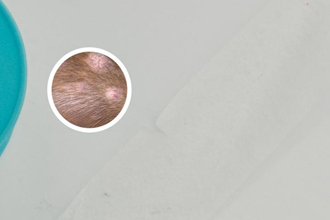

308激光的治療方式主要分為面照和局部照射。面照適用于大面積白癜風(fēng),局部照射則針對(duì)局限性皮損。

308激光的效果受多種因素影響,如皮膚類(lèi)型、皮損時(shí)間、皮損部位等。部分患者治療后可達(dá)到較高以上的有效率。